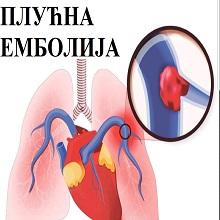

Дубока венска тромбоза ( phlebothrombosis ) настаје због призидног стварања тромба који својим растом може у потпуности да опструише венски лумен. Последично се развија дистална венска тромбоза. |

|

У првој недељи дубоке венске тромбозе тромб није чврсто фиксиран за зид и растреситог је састава. Део тромба се може откинути и пропагирати до пулмоналне артерије, ту се зауставља изазивајући емболију плућа (embolia pulmonum). |

Тромбоемболија плућа настаје опструкцијом гране плућне артерије крвним угрушком. Презентује се у виду отежаног или убрзаног дисања, убрзаног срчаног рада, несвестице и бола у грудима. |